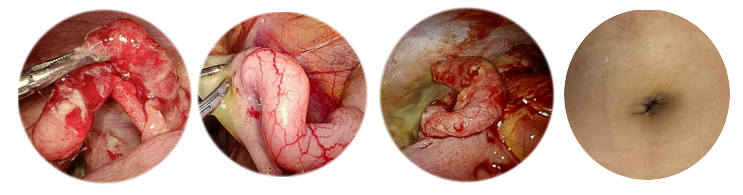

1.腹股沟斜疝

腹腔镜手术优势:切口小、疼痛轻、出血少、术后恢复快、愈合美观。

不解剖输精管和生殖血管,避免医源性隐睾。

可缩短手术时间。

不增加腹壁切口,同时探查对侧内环情况

同时处理双侧病变,避免异时疝再手术。

腹腔镜治疗小儿腹股沟斜疝有替代传统手术的趋势。